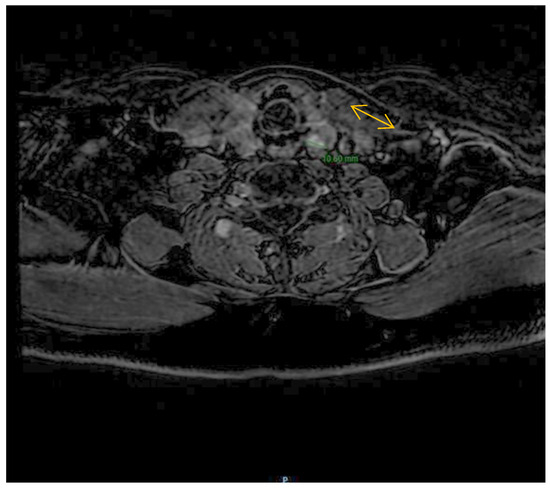

2.3. Imaging Findings